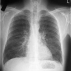

Грудная клетка приобретает бочкообразную форму (увеличена в объеме и как бы постоянно находится к положении глубокого вдоха), межреберные промежутки расширены и иногда выбухают, положение ребер приближается к горизонтальному, надключичные области сглаживаются или выбухают.

Дыхательные экскурсии грудной клетки уменьшены, в дыхании участвуют мышцы груди и шеи. При перкуссии(постукивании) грудной клетки выявляются коробочный звук. Аускультативно обычно определяется ослабленное везикулярное («ватное») дыхание. Тоны сердца, как правило, ослаблены. При пальпации брюшной стенки нередко удается определить безболезненный край печени, смещенный книзу вследствие опущения диафрагмы.

Медицинские процедуры, проводимые при заболевании эмфизема лёгких: Спиральная компьютерная томография, Спирография при записи на автоматических аппаратах, Легочная функция тест, Рентгенография легких